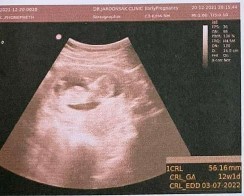

แบบนี้ น้องเป็นเพศไหนคะ คุณแม่ๆ☺️

สอบถามผู้รู้หน่อยคะ ญ รึ ช 🙏